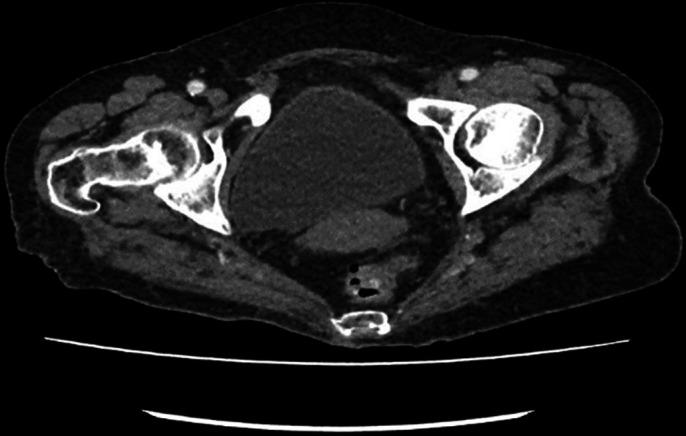

Histiocytic or xanthogranulomatous endometritis (XGE) is an extremely rare benign histopathological entity with only a few cases reported in literature to date. It is characterised by the replacement of endometrial tissue with sheets of foamy histiocytes, giant cells, lymphocytes and plasma cells; calcification and necrosis. It involves chronic inflammation and may be associated with endometrial hyperplasia, endometrial carcinoma and atrophy, causing cervical stenosis and recurrent pyometra, especially in postmenopausal women. We report a case of senile recurrent pyometra masquerading as pyelonephritis clinically and endometrial malignancy radiologically, confirmed later on histology as XGE. Due to deceptive manifestation and rarity of this clinical condition, it is very important for a gynaecologist, radiologist and histopathologist to have a clear understanding of this entity.

组织细胞性或黄色肉芽肿性子宫内膜炎(XGE)是一种极其罕见的良性组织病理学实体,迄今为止文献中仅报道了少数病例。其特征是子宫内膜组织被成片的泡沫状组织细胞、巨细胞、淋巴细胞和浆细胞取代;伴有钙化和坏死。它涉及慢性炎症,可能与子宫内膜增生、子宫内膜癌和萎缩相关,导致宫颈狭窄和复发性脓性子宫积脓,尤其是在绝经后女性中。我们报告一例老年复发性脓性子宫积脓病例,临床上伪装为肾盂肾炎,放射学上疑似子宫内膜恶性肿瘤,后来经组织学确诊为XGE。由于这种临床情况的表现具有欺骗性且罕见,妇科医生、放射科医生和组织病理学家清楚了解这一实体非常重要。